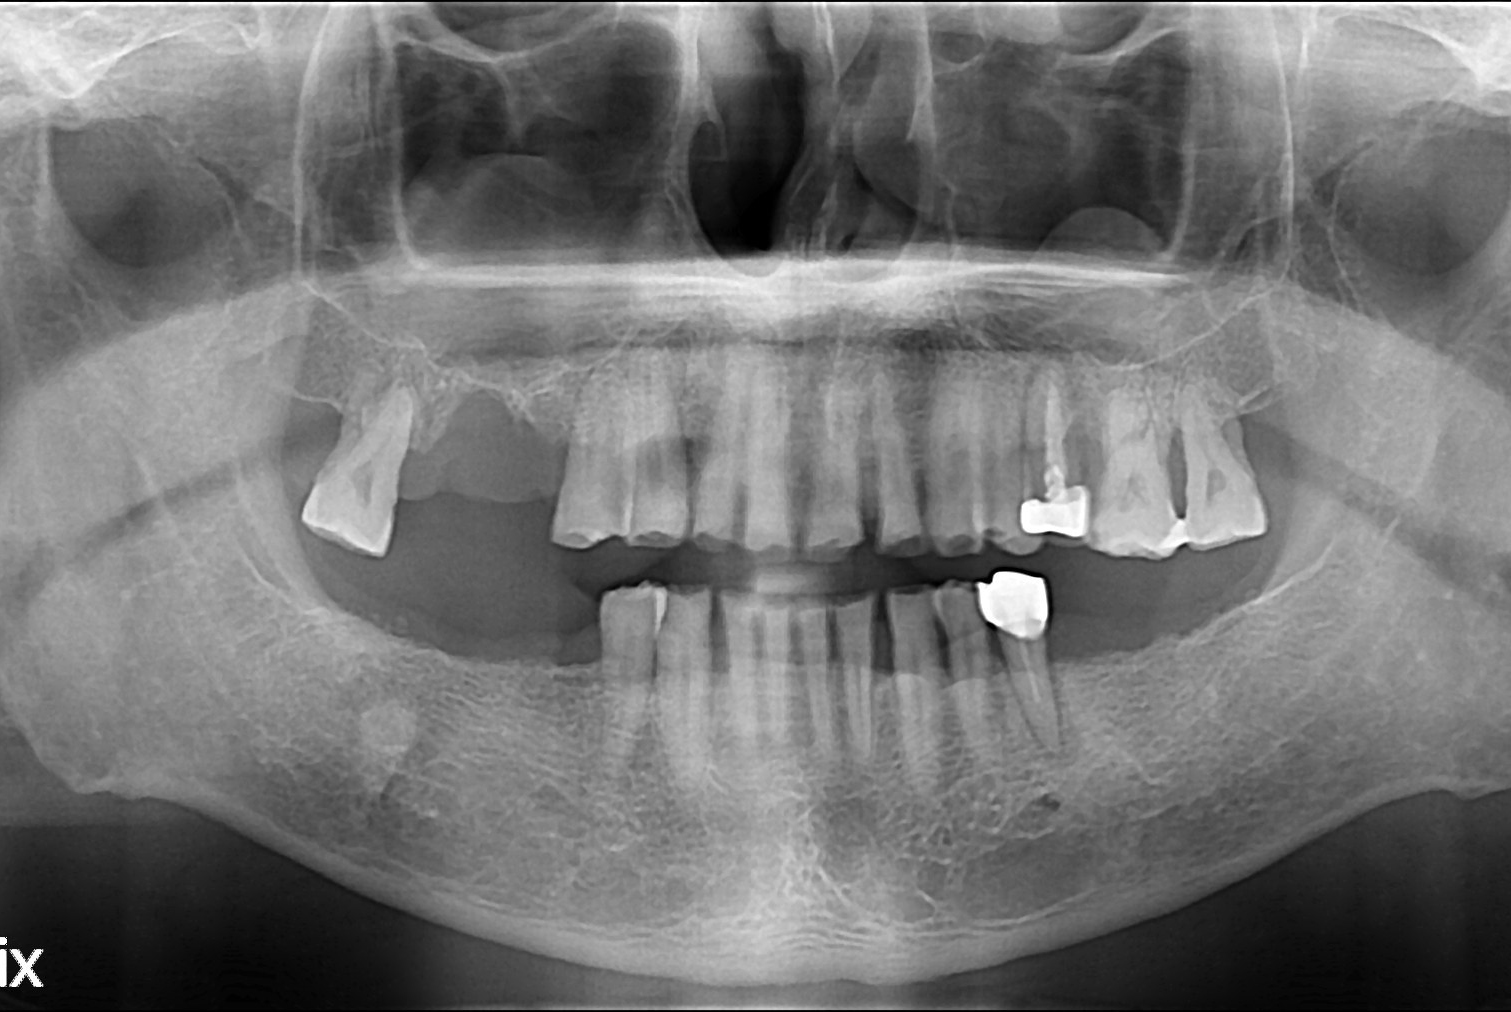

치료전 : 2018-07-18

세종치과는 많은 환자와 다양한 케이스를 바탕으로 항상 편안한 임플란트 수술을 제공하고자 노력하고,

오래동안 튼튼히 쓸 수 있는 임플란트 수술을 가장 큰 목표로 삼고 있습니다